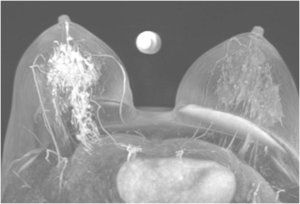

Bilateral Mammograms revealed increased reticular densities in the upper half of the right breast. A 16 mm well defined nodule seen in the left subareolar region. BIRADS 3/4 Bilateral breast ultrasound revealed extensively dilated ducts showing thickened walls and intra ductal contents corresponding to the increased reticular densities on the mammogram of right breast. Left breast revealed a 17 x 10 mm well defined low echogenic lesion with posterior enhancement in the left subareolar region. BIRADS 3 MRI showed segmental clumped / clustered ring enhancement extending from 10 to 2 O’ clock position in the right breast with extensive ductal branching and intraluminal contents extending till the nipple suspicious for DCIS. Left breast revealed a benign 16 x 14mm well defined nodule in the lower inner quadrant close to the nipple. BI-RADS-4.